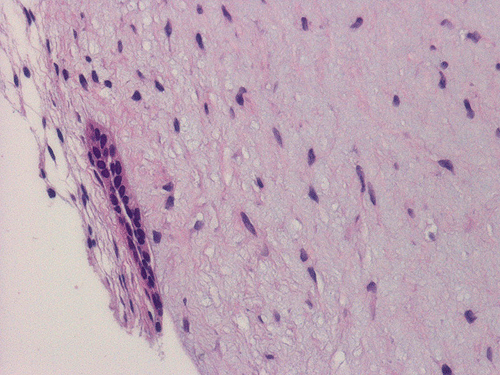

The biopsy material contained several small cores of tissue. Panel B is a low-magnification photo that showed a myxomatous lesion on one side with some linear mature bone trabeculae on the other side. This area probably represented the thinned out residual cortical bone. Panels C and D are higher magnification photos of the bone trabeculae in Panel B. No osteoclastic activity is evident. Panel E shows small, mature bone spicules that are surrounded by myxomatous tissue. The hypocellular and myxomatous nature of the lesion is well demonstrated in Panel F. Panel G and H are high magnification photos from different areas and show a modest number of collagen fibers within a myxomatous background. The bland features of the tumor cells are also well illustrated.

Macroscopically, MOJs have a gelatinous, loose texture and may be covered by a thin shell of cortical bone that has been eroded by the tumor. Histologically, they are typically hypovascular and hypocellular. The lesional tissue is composed of small, stellate or spindle-shaped cells in a myxomatous background. Nuclei are usually small and hyperchromatic; mitotic figures are lacking. Scattered small islands of odontogenic epithelial cells that usually appear inactive  are present 6. Histochemically, the myxomatous ground substance contains acid mucoploysaccharide, chiefly hyaluronic acid and chondroitin sulfate. This be well demonstrated by alcian blue stain. A few delicate collagen fibrils are typically present. Some cases may have an increased amount of collagen and they are sometimes termed fibromyxoma. There is no evidence, however, that these tumors behave differently.